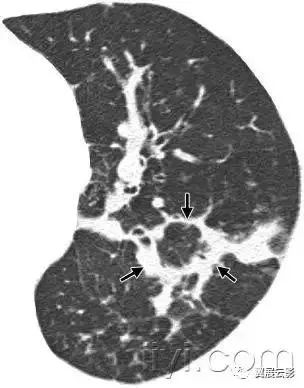

十八、小叶中心性:

解剖:小叶中心性用于描述次级肺小叶的支气管血管束中心区域。病理学上也用这一术语描述终末小支气管远端,位于呼吸性细支气管和肺泡管中心的病变。

CT:正常次级肺小叶中心的点状或者线状的密度增高影,胸膜下25px范围内最明显,代表小叶内的动脉,直径约1mm。

小叶中心性异常包括(1)结节(2)树芽征,提示小气道病变(3)由于临近间质的增厚或者浸润导致小叶中心结果更加清晰(4)小叶中心性肺气肿导致的异常低密度。

附图为小叶中心性肺气肿